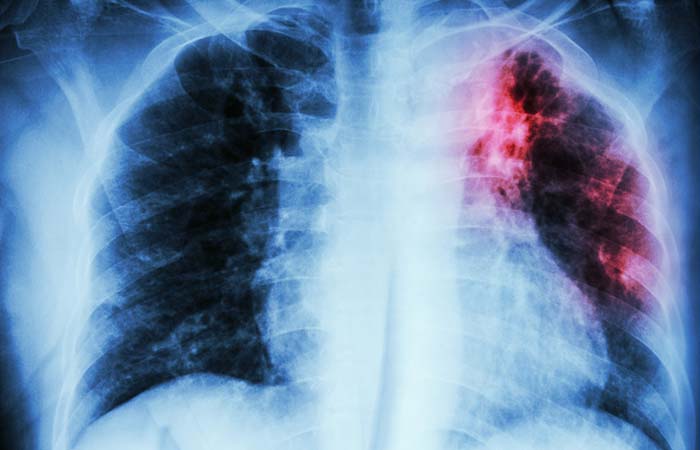

Limit TB drugs to one month’s supply, warns MHRA amid shortages

Supplies of a number of antimicrobials used to treat tuberculosis will be ‘intermittent’ until at least the end of the year, the MHRA has warned as it advised prescribers to limit prescriptions to a maximum of one month’s supply.

A national patient safety alert issued by the MHRA on Tuesday July 29 revealed that seven TB antimicrobials have been affected by shortages, including three Rifampicin products and certain strengths of Rifinah, Rifater, Voractiv and Pyrazinamide tablets.